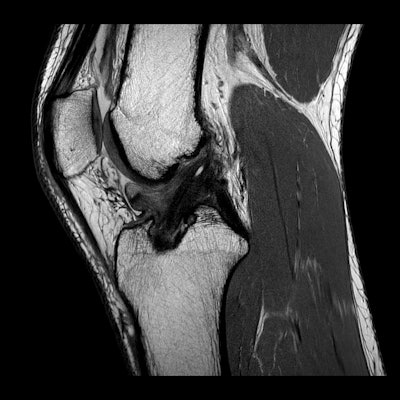

AFL (Australian Football League) football, rugby, and netball account for most injuries -- much more than, say, soccer, basketball, and cricket. As the physical demands of these sports have changed, we see many more muscle injuries (particularly hamstring and calf) than before. In the last five years, we have seen more women transition over to football and rugby. As a consequence, we are seeing many more injuries in the female population than before; these include muscle tears, shoulder dislocations, and anterior cruciate ligament (ACL) rupture. The incidence of ACL rupture in AFL football for women is nine times that of the male population, which is quite worrisome.

As a diagnostic tool, MRI has superseded both ultrasound and radiographs. For example, we typically perform 80 musculoskeletal MRI scans per day but perhaps fewer than 10 radiographs. There is a broad mix of all the joints. We are now quite confident in assessing muscle injuries and providing accurate information about when an athlete might return to play and the risk of a recurring injury. For intervention, fluoroscopy has become redundant, and we would typically perform 50 to 60 interventions per day under ultrasound or CT guidance.